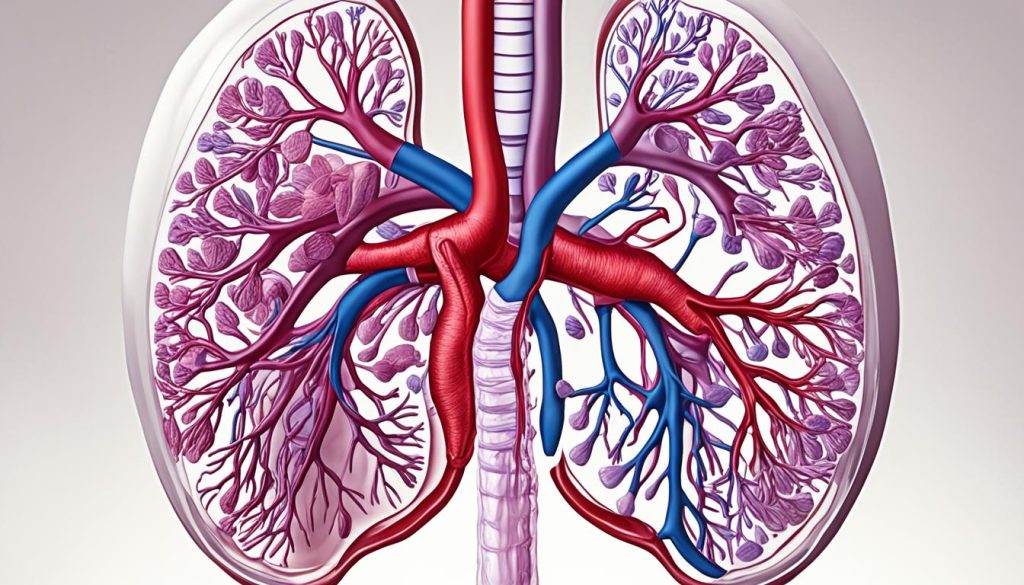

The liver gets its blood from two main sources: the hepatic artery and the portal vein. The hepatic artery brings oxygen-rich blood from the heart. The portal vein carries nutrient-rich blood from the digestive system. This mix of blood is key for the liver’s many tasks.

The liver has special systems for blood and bile flow. The vascular system, with veins and arteries, keeps blood moving for nutrient processing and cleaning. The biliary system, with bile ducts, sends bile to the gallbladder and small intestine to help with digestion.